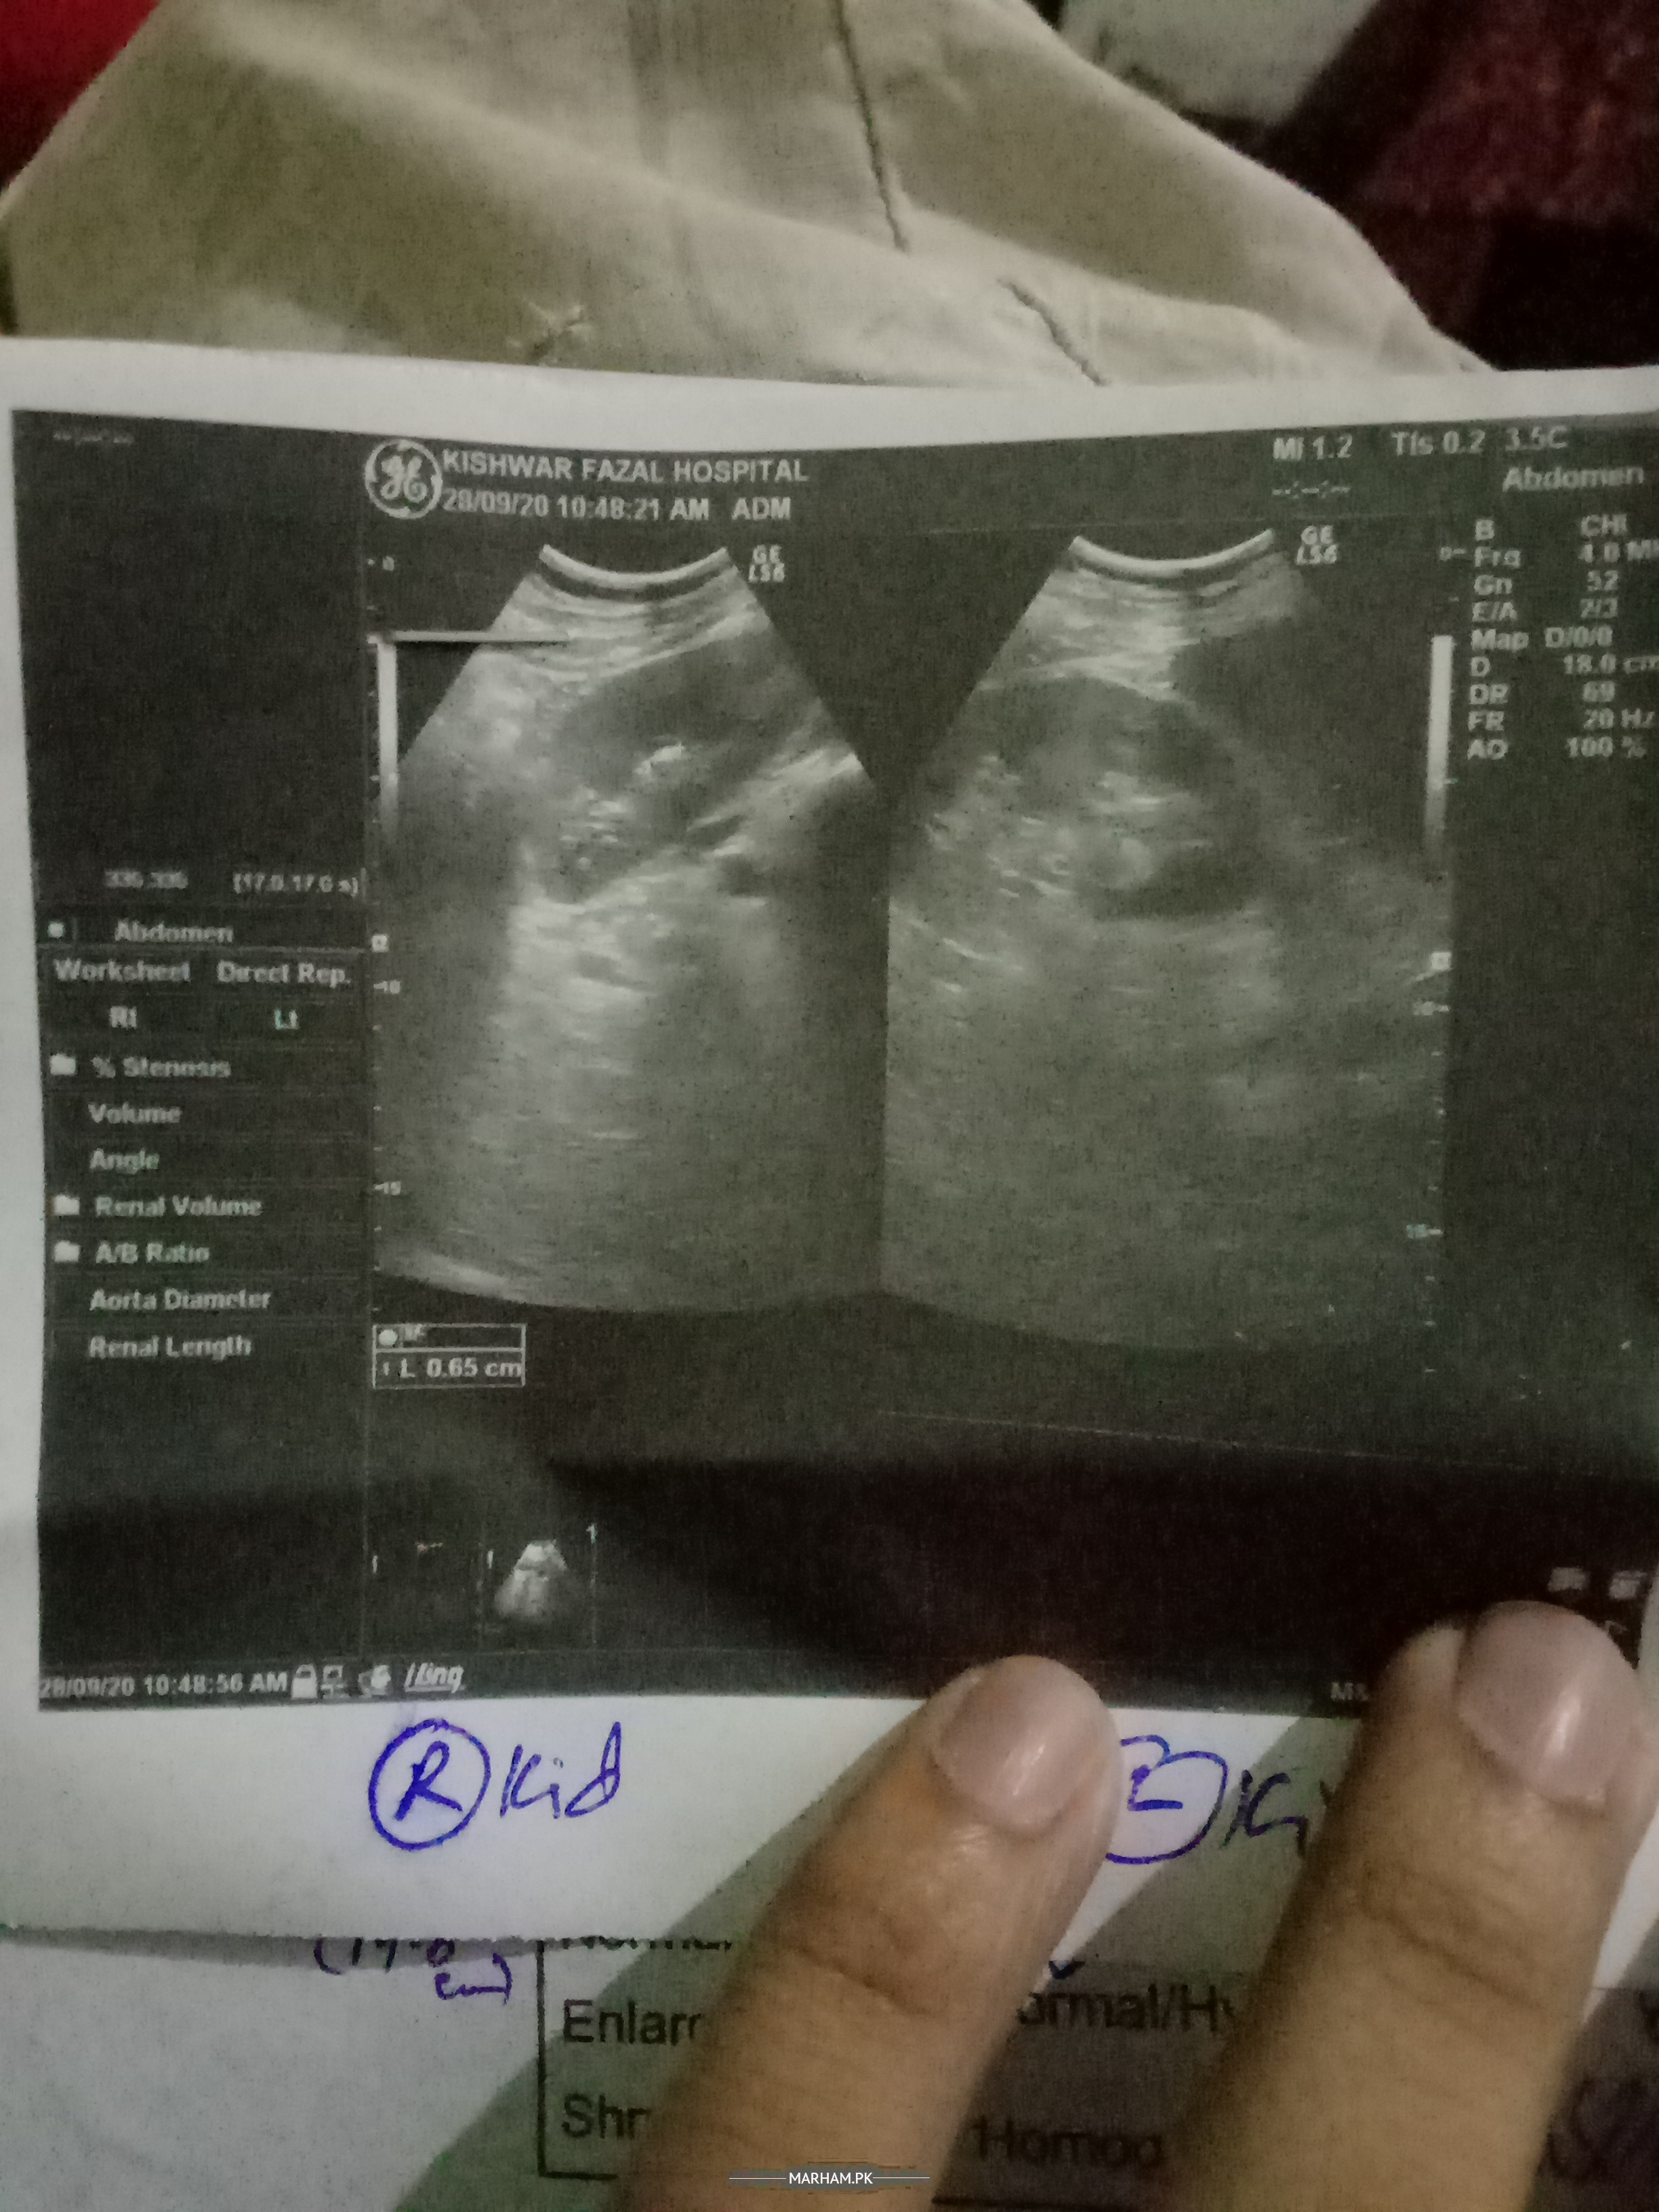

post your ultrasound report depends on size location type of stone treatment consult online through provided portal

ultrasound